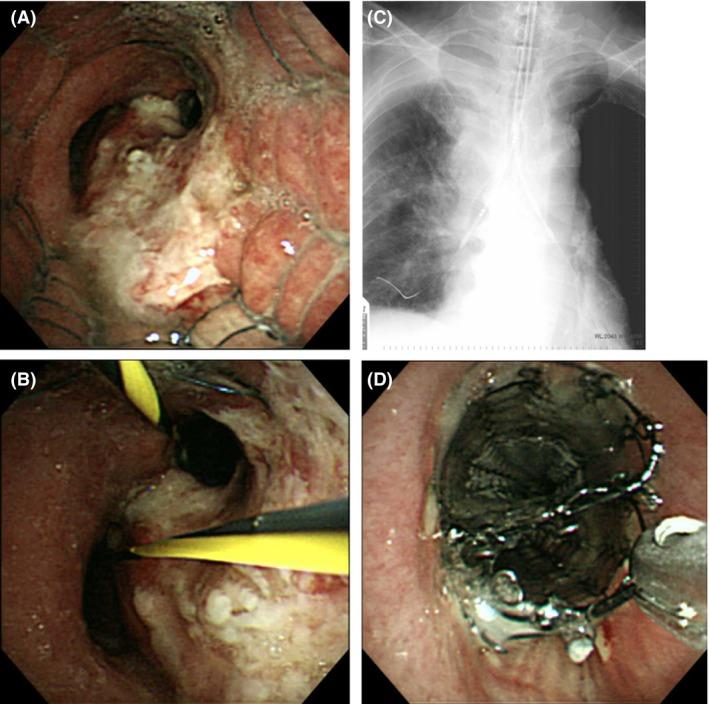

采用自膨式金属支架“并排”法并联合化疗成功治疗恶性隆突受累。

Successful management of malignant carinal involvement by "side-by-side" method of self-expandable metallic stents followed by chemotherapy.

Bilateral self-expandable metallic stents may be useful in the management of malignant carinal involvement and may improve the performance status of patients. This strategy may allow patients with poor performance status to receive additional chemotherapy.

摘要